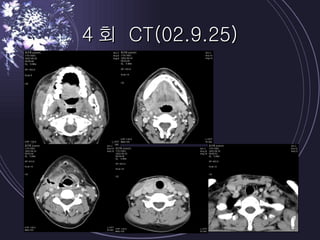

4회 CT(02.9.25)

Case report 1Pt ; 38/F CC ; 내원 5 일 전 개인치과 발치 후 우측 swelling 으로 내원 PI ; mouth opening limitation, dysphagia, Rt buccal & sub mn swelling / Td/ redness Dx ; masticatory spce, lat. Pharyngeal space abscess Tx ; I & D X 2 (submn & submental, deep neck carotid sheath area) anti theraphy ( aug + micronomycin + flagyl) fluid etc supplementary tx (O2 etc) 초진 lab ; WBC 30260, segmental neutrophil 85.9%, CRP 36.5